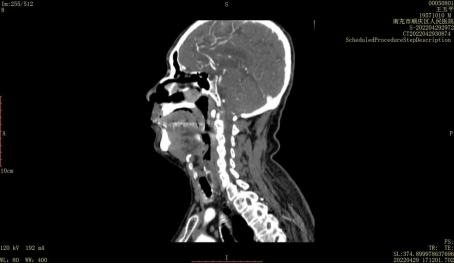

今年70岁的张爷爷因头晕伴视物旋转、伴行走不稳、反应稍迟钝,左侧头部及右侧肢体轻微胀痛无力而来到顺庆区人民医院内一科住院,内一科医生在了解病情后随即为患者开具了头颈联合CTA检查,检查结果显示该患者左侧椎动脉颅内段闭塞,影响了脑组织血养供应,继而引起了相关的症状。明确病因后,医生对其给予了对症治疗,在多方的协同配合下,张爷爷的病情很快逐渐好转。

顺庆区人民医院放射科开展的CTA即CT血管成像,是经静脉注入特殊的对比剂,利用多层螺旋CT在受检者血管内对比剂充盈高峰期(也就是看起来最白的时候)时进行连续的扫描成像展示出有问题的地方。MSCTA在提供血管形态学方面的同时,还可以通过高级血管分析软件对患者病变血管的狭窄程度、范围进行评估,同时能够清楚的显示管腔内的斑块并初步评估,为临床诊治提供重要参考。